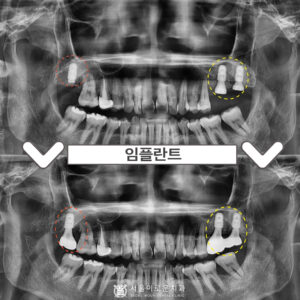

부천중동치과 발치 즉시 임플란트를 하고 싶다면? 안녕하세요 😀 이에 좋은, 이로움을 알리는 서울 이로운 치과입니다. 오늘은 ‘발치즉시 임플란트’에 대해 소개해드리려 합니다. ^^ 발즉 임플란트란? 당일 발치 후 바로 임플란트를 식립하는 것을 의미하는데요. 치료기한이 단축된다는 장점이 있으나, 상황에 따라 안정적이라는 판단하에 가능한 경우에만 시행하고 있습니다 🙂 왼쪽 아래 치아가 콕콕 쑤시고 더보기…